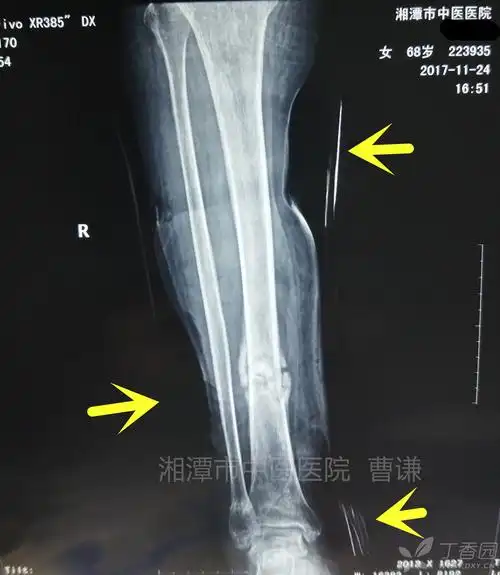

胫骨骨髓炎陈旧骨折如何治疗? [病例帖]